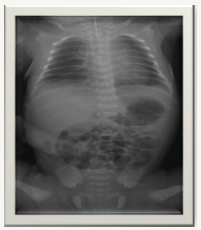

f) He was admitted to the NICU for management of prematurity and respiratory support (Figure 1).

Figure 1:

g) His initial chest x-ray was unremarkable. Started on IV Ampicillin and Gentamicin owing to high risk of infection but were discontinued after 48 hours as he remained well and sepsis screen was normal along with sterile blood culture.